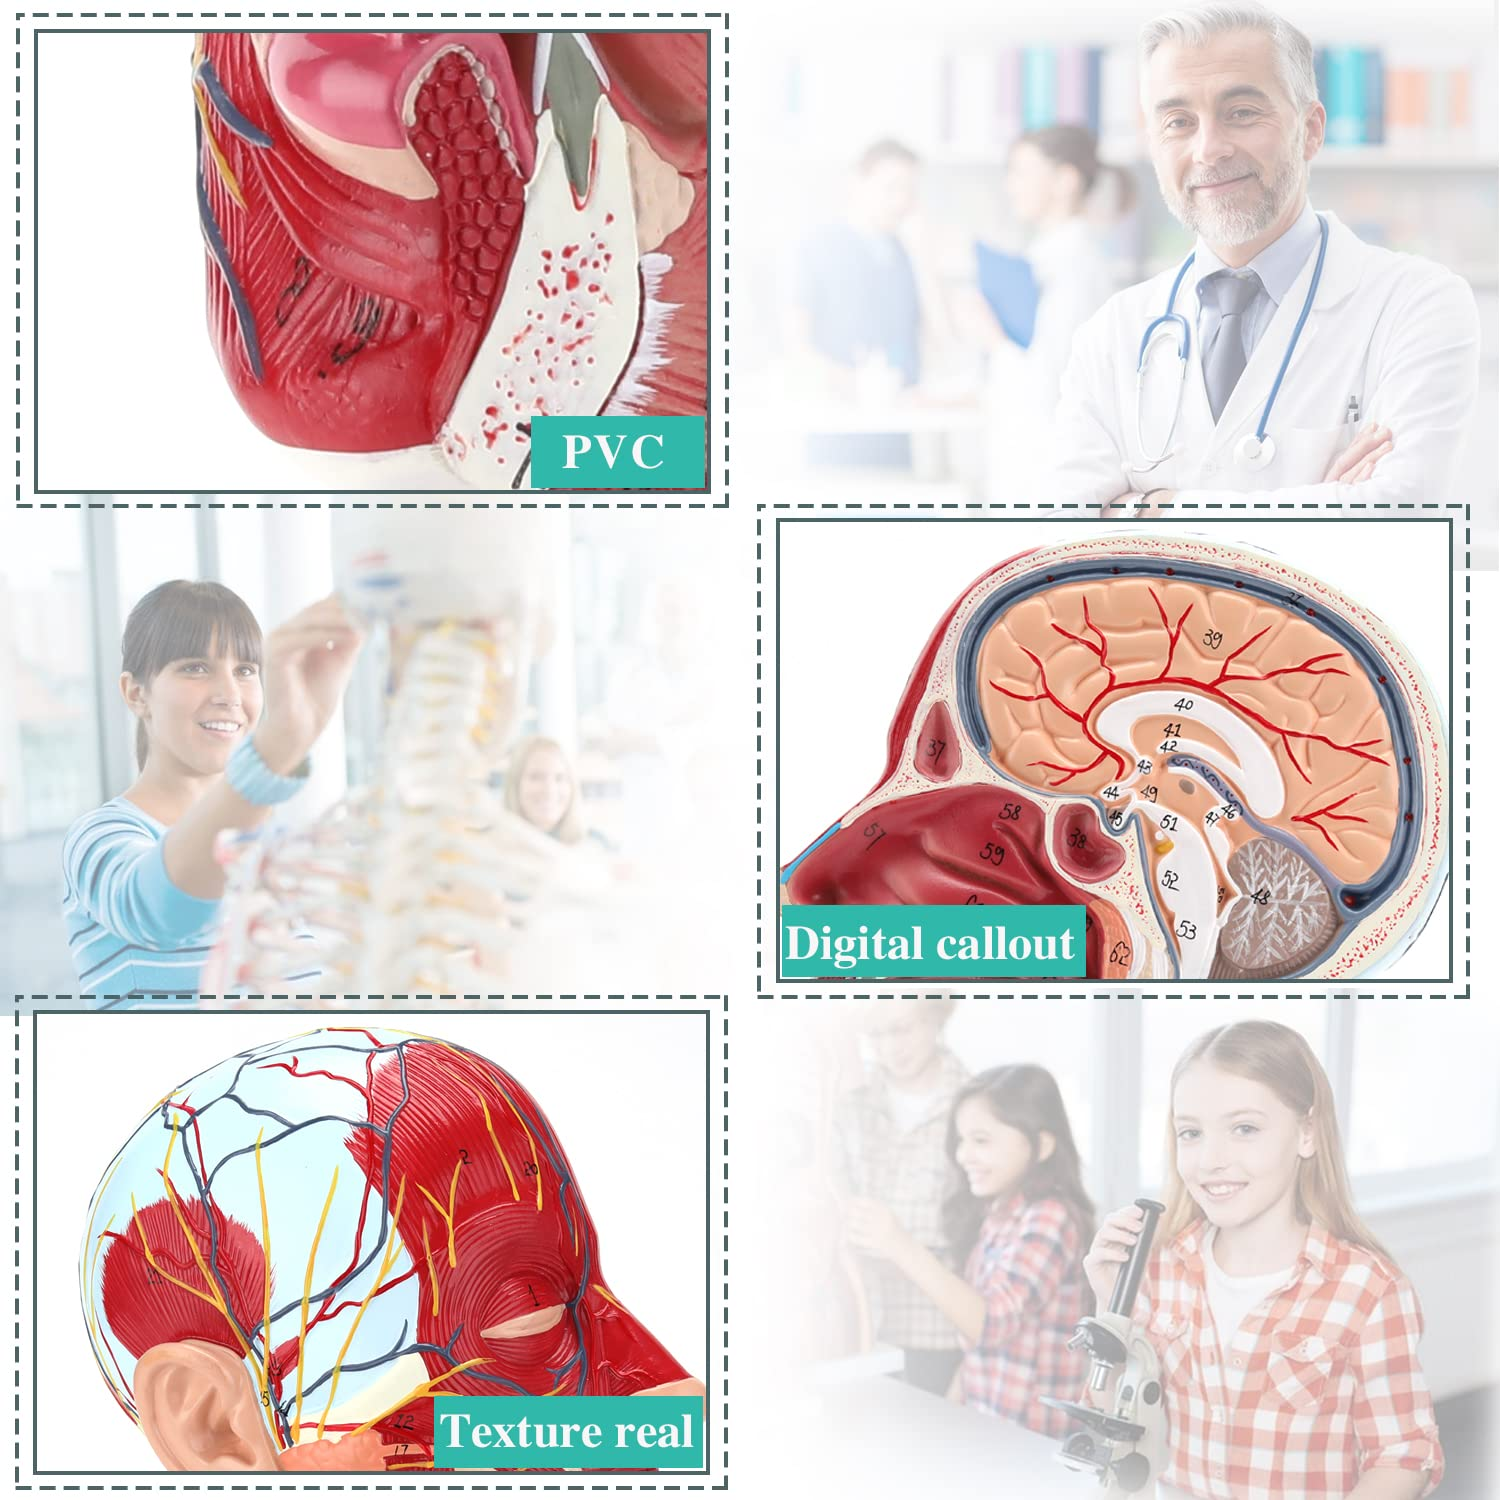

| Material | PVC |

【High Quality】Brain anatomy model, made of non-toxic environmentally friendly PVC material, easy to clean. Anatomy models are hand-painted and assembled with the utmost attention to detail.

【Superficial Neurovascular Muscle Model】Highly detailed, numbers marked, detachable ear, deepen the understanding of the superficial muscles, vessels, nerves and the internal structures of the head & neck. Red-artery, blue-vein, yellow-nerve.